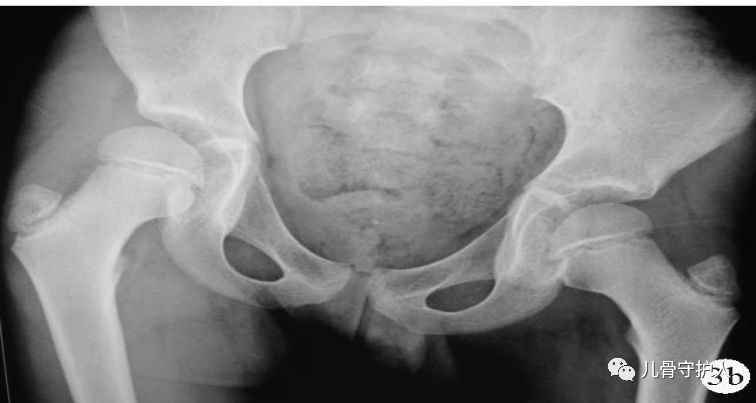

4.X:骨盆轻度倾斜,髋关节囊肿胀,关节间隙增宽,无骨质破坏。B超:患髋股骨颈颈前间隙增宽,双侧差值大于1mm。滑膜增厚,关节积液。